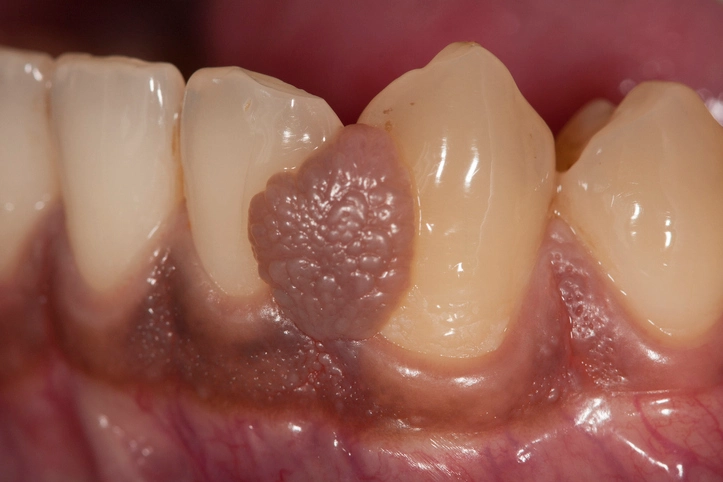

Kaposi’s Sarcoma

Etiology

Kaposi’s sarcoma is a vascular malignancy associated with human herpesvirus-8 infection and immunosuppression, particularly in individuals with HIV/AIDS.

Oral Features

- Red, purple, or brown macules, plaques, or nodules

- Commonly affects the palate and gingiva

- May ulcerate or bleed

Clinical Importance

Oral Kaposi’s sarcoma may be an early sign of underlying immunodeficiency. Management involves oncologic and medical treatment, often with good response to radiotherapy.